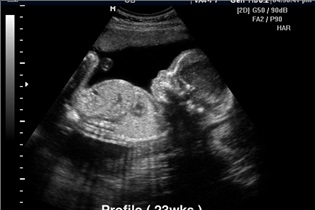

نی نی سایت:یکی از سئوالات زنان باردار این است که اگر در هفته شانزدهم بارداری جنین خود را سفت کند ولی بعد از چند ثانیه خود را رها کند مشکلی وجود دارد،دکتر آرین -جراح و متخصص زنان، زایمان و نازایی در این‌باره تشریح کرد: سفت کردن جنین چیزی نیست که به وسیله مادر حس شود این حالت مربوط به رحم است که با انقباض حالت سفتی و درد حس می‌شود که اکثراً بر اثر عصبانیت‌های شدید ایجاد می‌شود و گاهی نیز اگر حاملگی با فیبروم همراه باشد حس می‌شود در هر حال با یک بار اتفاق مشکلی پیش نمی‌آید ولی اگر متداوم و تکراری باشد حتماً با پزشک خود در میان گذاشته شود چون ممکن است باعث پارگی کیسه آب یا خونریزی پشت جفت شود که نتیجه آن زایمان زودرس خواهد بود.در این راستا یکی دیگر از سئوالات زنان این است که چه مدت بعد از فریز کردن زخم دهانه رحم می‌توان برای بارداری اقدام کرد که این جراح و متخصص زنان، زایمان و نازایی در این‌باره تشریح کرد: بهبودی زخم دهانه رحم بعد از فریز کردن در افراد مختلف متفاوت است و قاعدتاً تا یک ماه باید زخم فریز شده ترمیم یافته و طبیعی شود.در هر حال حاملگی بعد از فریز کردن هر زمانی می تواند حادث شود و نیازمند زمان بندی خاصی نیست.این جراح و متخصص زنان، زایمان و نازایی تصریح کرد: براین اساس برای اطمینان بیشتر بهتر است یک تا دو ماه بعد به وسیله پزشک کنترل شود تا بهبودی کامل مشخص شود زیرا با یک بار فریز کردن زخم کاملاً بهبود نیابد.